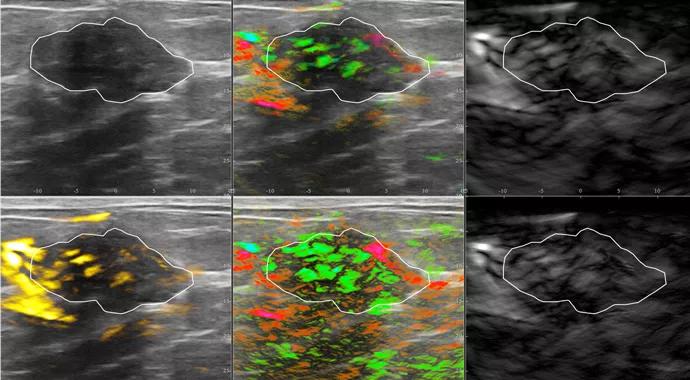

The Imagio® breast imaging system is based on the technology of opto-acoustic imaging (OAI). “It is a combination of optical imaging, which is light, and sound imaging, which is ultrasound,” says Stephen Grobmyer, MD, Cleveland Clinic’s principal investigator for the clinical trial, Director of Surgical Oncology and Director of the Breast Center. “That combination gives a unique way to look at tissue.”

Instead of radiation, the technology sends pulses of safe near-infrared light that penetrate breast tissue. The light creates sound waves within the tissue that are detected by an ultrasound transducer.

The Imagio OAI system currently under study at Cleveland Clinic and other sites uses two specific light wavelengths. At one of these wavelengths, the strongest absorber of light is oxygenated hemoglobin. At the other, deoxygenated hemoglobin absorbs the light most strongly.

“When you use those two different wavelengths, you can create a map of oxygenated blood and deoxygenated blood within tissue,” Dr. Grobmyer explains. “This technology is providing us with functional imaging based on the amount of oxygenated/deoxygenated blood within a lesion and provides us with information about metabolism and oxygen exchange without using any contrast agent at all.”

Cancerous tissue tends to have a higher metabolic rate and extract oxygen from blood more readily than does normal resting tissue. The combination of hemoglobin concentration and relative oxygenation is intended to aid differentiation between malignant and nonmalignant lesions. “We are hoping that by looking at the pattern of oxygenated/deoxygenated blood, along with the image of the lesion, we can better predict which masses are more likely to be cancerous and non-cancerous,” he says.

Image courtesy of Seno Medical Instruments, Inc.